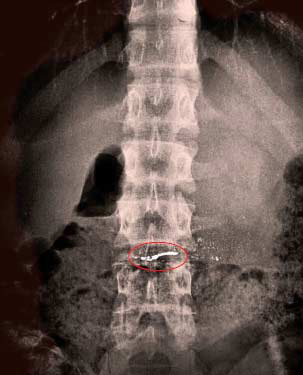

工商部门随后下发了《关于对吉林达利食品有限公司生产的达利园派实施原地封存措施的紧急通知》。但具体水银是怎么进入蛋糕内的,至今还是疑问。

“2号那天,11点多下课我饿了,同桌给我了一个达利园派,根本没注意,就一口吃掉了一半,后来上课老师进来了,我把剩下的一半一把塞嘴里了。等说‘老师好’的时候,一个小亮珠从我嘴里掉在了铺在桌子上的衣服上。我当时看着好像是水银,同桌看说也像水银。”随后许工凡让同桌看自己的嘴,结果同学发现他的嘴里也有很多亮晶晶的物体,因为知道水银有毒,害怕的许工凡一口把嘴里的物品吐掉。

因为当时正是物理课,物理老师看后认定确实是水银,立即让许工凡去了医务室。“医务室的老师看后也证实是水银。”班主任老师打电话找了家长。